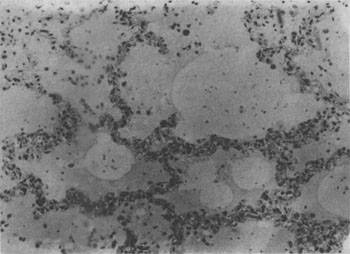

发生水肿的组织,体积增大,颜色苍白,镜下可见水肿液积于细胞和纤维结缔组织之间或腔隙内。由于水肿液含血浆蛋白,故HE染成粉红色。肺水肿时,肺泡腔内充满水肿液(图3-16)。切开肺时可有泡沫状液体自切面溢出。脑水肿时脑回变扁平,脑沟变浅。镜下,脑灰质和白质疏松,血管周围间隙加宽。严重时脑组织在高倍镜下呈网化状态。严重脑水肿时可形成脑疝。

图3-16 肺水肿

肺泡腔内有水肿液及漏出的红细胞,肺泡壁毛细血管扩张充血